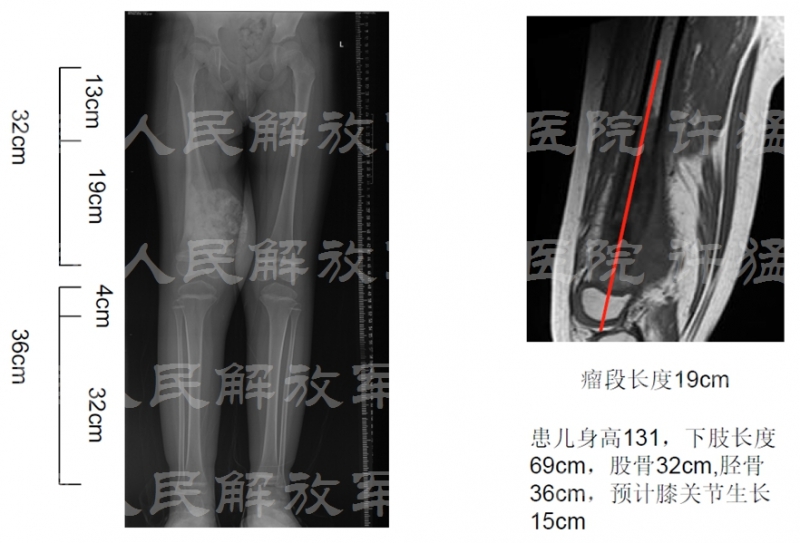

治疗前相关检查: